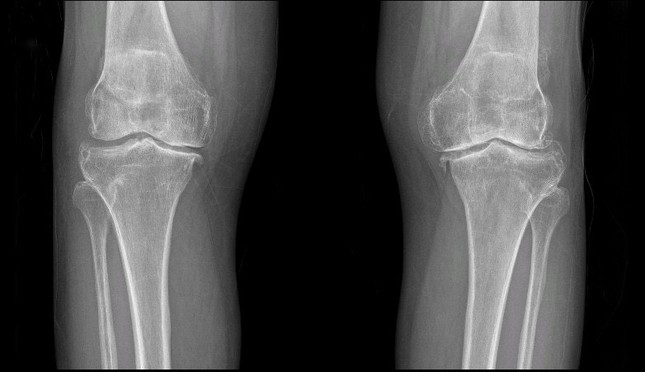

Hình ảnh thoái hóa khớp gối trên phim chụp Xquang

TS.BS Lê Quang Huy (Trưởng Đơn nguyên chấn thương chỉnh hình - BVĐK Hồng Ngọc) - bác sĩ trực tiếp thăm khám cho bà Liên chia sẻ: “Cả hai khớp gối của bệnh nhân bị thoái hóa giai đoạn IV kèm biến dạng vẹo trong rất nặng. Phần lớn lớp sụn khớp đã bị hao mòn và không còn nguyên vẹn, khe khớp giữa hai đầu xương hẹp đáng kể, xuất hiện nhiều gai xương. Điều trị bảo tồn bằng thuốc và các thủ thuật nội khoa hiện không còn hiệu quả nên tối ưu nhất là phẫu thuật thay khớp gối nhân tạo để khôi phục lại vận động cho bệnh nhân.”